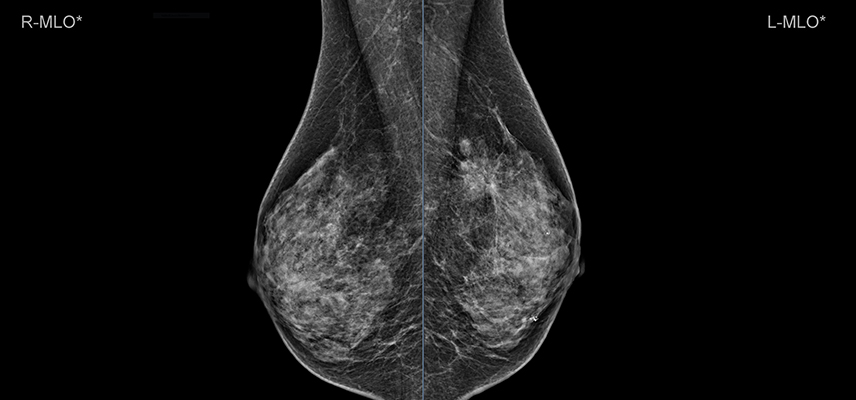

Sie bildet neben der Sonographie, die Basis der radiologischen Brustdiagnostik. Bei der Mammographie wird die Brust mittels Röntgenstrahlung dargestellt. Normalerweise werden je Brust zwei Aufnahmen aus unterschiedlichen Winkeln angefertigt.

Normalerweise werden von jeder Seite zwei Aufnahmen angefertigt, um eventuell vorhandene krankhafte Prozesse in zwei Ebenen darzustellen und innerhalb der Brust lokalisieren zu können. Bei einigen Befunden müssen zusätzliche Aufnahmen erfolgen, um eine auffällige Veränderung deutlicher darzustellen (z. B. Vergrößerungsaufnahmen bei sehr kleinen Befunden).